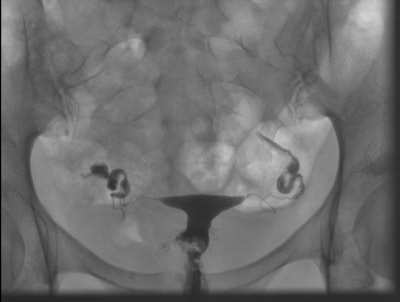

A 32-year-old patient with symmetrically separated uterine cavity (uterus septus). Also, notice venous intravasation of the contrast medium. Laparoscopy and hysteroscopy were performed, and the septum was resected. After this procedure, the patient was lost to follow-up.The detection rate for pathologies using HSG was low (21%) and the false-positive rate was high (39%), the researchers concluded.